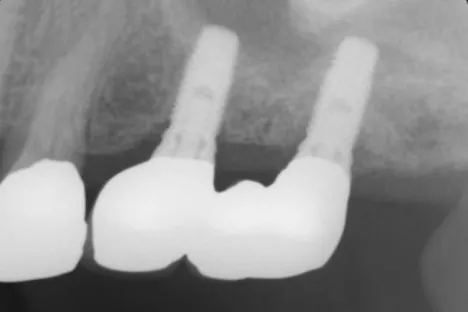

Dr.Tachikawa_Fig.8

Fig. 8. Dental X-ray photograph of the same. The implant is clinically and radiologically stable.